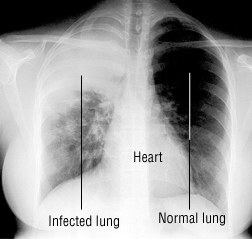

受感染的肺部与正常肺部对比。/ drugs.com